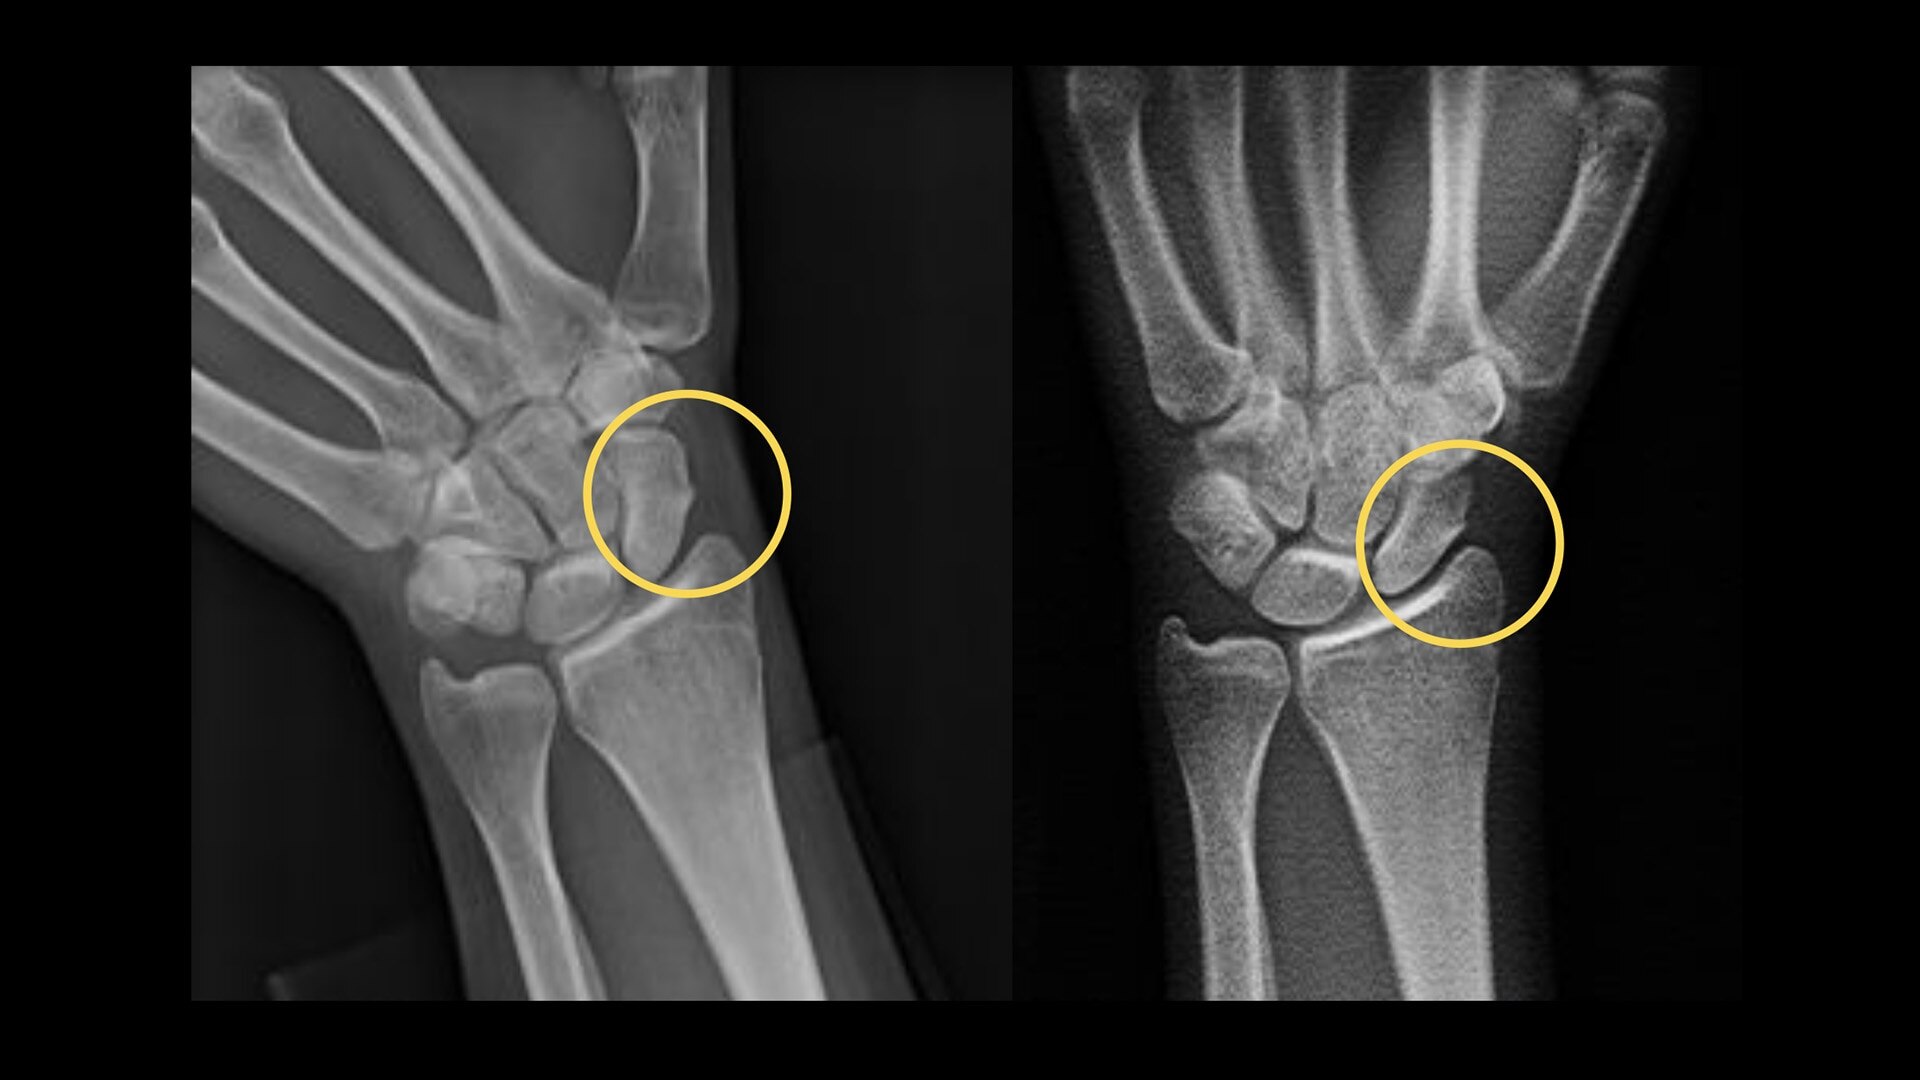

Your department relies on standard radiography as the first diagnostic test for most chest, orthopedic and trauma cases. But hairline fractures or non-displaced fractures are difficult to detect on conventional X-rays.13 According to a recent study, 33% of scaphoid fractures are missed on the first X-ray.14

Sensitivity in the detection of scaphoid fractures on average6,7

80%